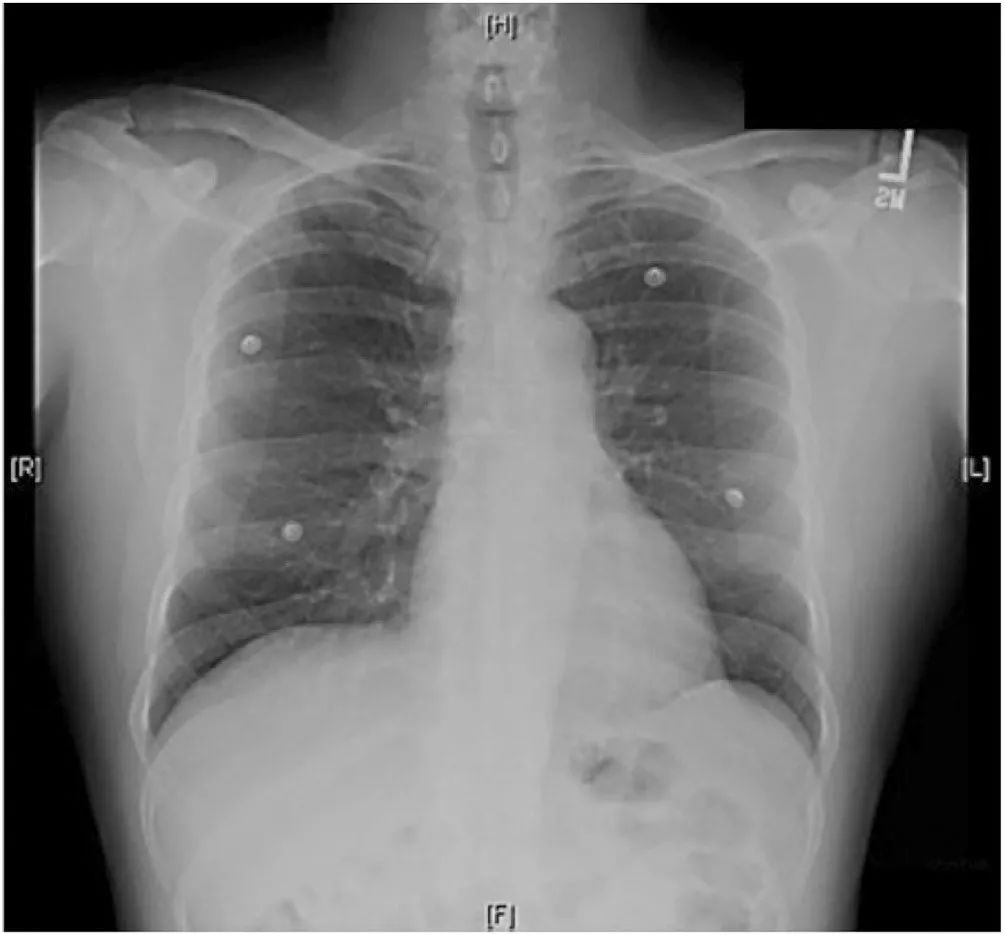

图1 胸片心影正常,无肺部疾病。